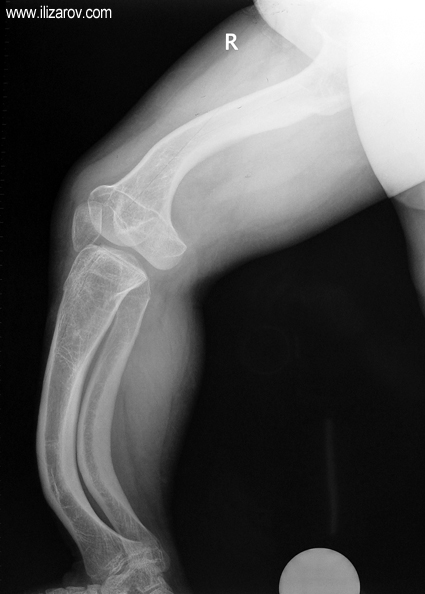

Hipofosfatemik raşitizmde anormal kemik bulguları 1 yaşından sonra belirginleşir; kısa boy ve sıklıkla diz çevresinde deformiteler (bilateral genu valgum ya da varum, tibial torsiyon, femur ve tibiada eğrilik, ‘windswept’ deformitesi) ortaya çıkar.

Hipofosfatemik raşitizmin neden olduğu bozukluk büyüme plağına çok yakın olduğu için büyük bir deformite ve ciddi dizilim bozukluğu ortaya çıkar. Bu nedenle cerrahi öncesi değerlendirmede sıklıkla birden çok deformite merkezi (CORA) bulunur ve deformitenin düzeltilmesi için birden çok seviyeden osteotomi yapılması gerekir. Deformitenin düzeltilmesi için en sık kullanılan yöntemler Ilizarov yöntemi ya da monolateral eksternal fiksatör kullanılarak akut ya da tedrici deformite düzeltilmesidir. Kliniğimizde uygulanan fiksatör yardımlı çivileme yönteminde deformite eksternal fiksatör kullanılarak akut olarak düzeltildikten sonra intramedüller çivi ile stabilizasyon sağlanmakta, uzatma yapılmayacaksa eksternal fiksatör cerrahi sona ermeden çıkartılmakta, uzatma yapılacaksa (çivi üzerinden uzatma) uzatma tamamlandıktan sonra fiksatör çıkartılmaktadır. Bu sayede tel dibi enfeksiyonu riski ortadan kalkmakta, hipofosfatemik raşitizm tedavisinde önemli sorunlar olan koreksiyon kaybı ve deformite nüksü önlenmekte, hastaya erken hareket verilerek tam yükle yürümesine izin verilmekte ve eksternal fiksatör süresi azaldığı için hasta konforu artmaktadır.